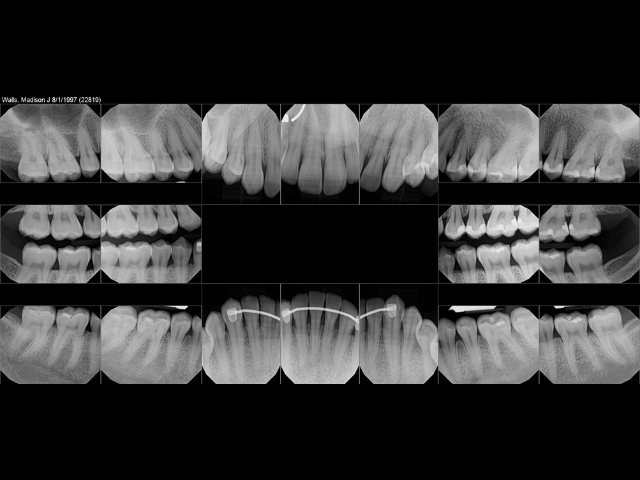

Good dental care begins with understanding what is happening beneath the surface. Full Mouth Digital X-rays, also called FMX, give a complete overall look at the teeth, gums, and jaw so patients and dentists can see the full picture of oral health. When patients receive Full Mouth Digital X-rays (FMX) at Brady Dental Group in Amarillo, Texas, they get clear, detailed images that support early detection, accurate diagnosis, and long-term care. This kind of imaging is one of the most important tools used in modern dentistry because it helps identify problems before they become painful or expensive to fix.

Full Mouth Digital X-rays include a series of detailed images that capture the entire mouth. This includes each tooth, every root, and the surrounding bone structure. The images are taken from different angles so the dentist can see areas that are not visible during a normal visual exam.

At Brady Dental Group in Amarillo, Texas, the FMX set usually includes images that show decay between teeth, infections near roots, bone loss, gum disease, dental restorations, and early signs of damage that could lead to future problems.

Early detection is one of the most valuable benefits of Full Mouth Digital X-rays. FMX can reveal hidden decay, bone loss that indicates gum disease, cysts, infections, and other issues that may not cause symptoms at first. When these problems are found early, treatment is simpler, less invasive, and more affordable.

FMX also helps dentists find patterns. For example, if several areas show early bone loss, it may indicate developing periodontal disease. If a certain tooth shows slow deterioration over time, FMX comparisons help guide treatment decisions. This long-term tracking supports better outcomes and helps patients stay ahead of potential problems.

Full Mouth Digital X-rays at Brady Dental Group use advanced software that creates clear and detailed images. The technology allows the dentist to measure bone levels, check the shape of roots, and compare changes from previous visits. This accuracy improves diagnosis and helps the dentist create treatment plans that support long-term success.